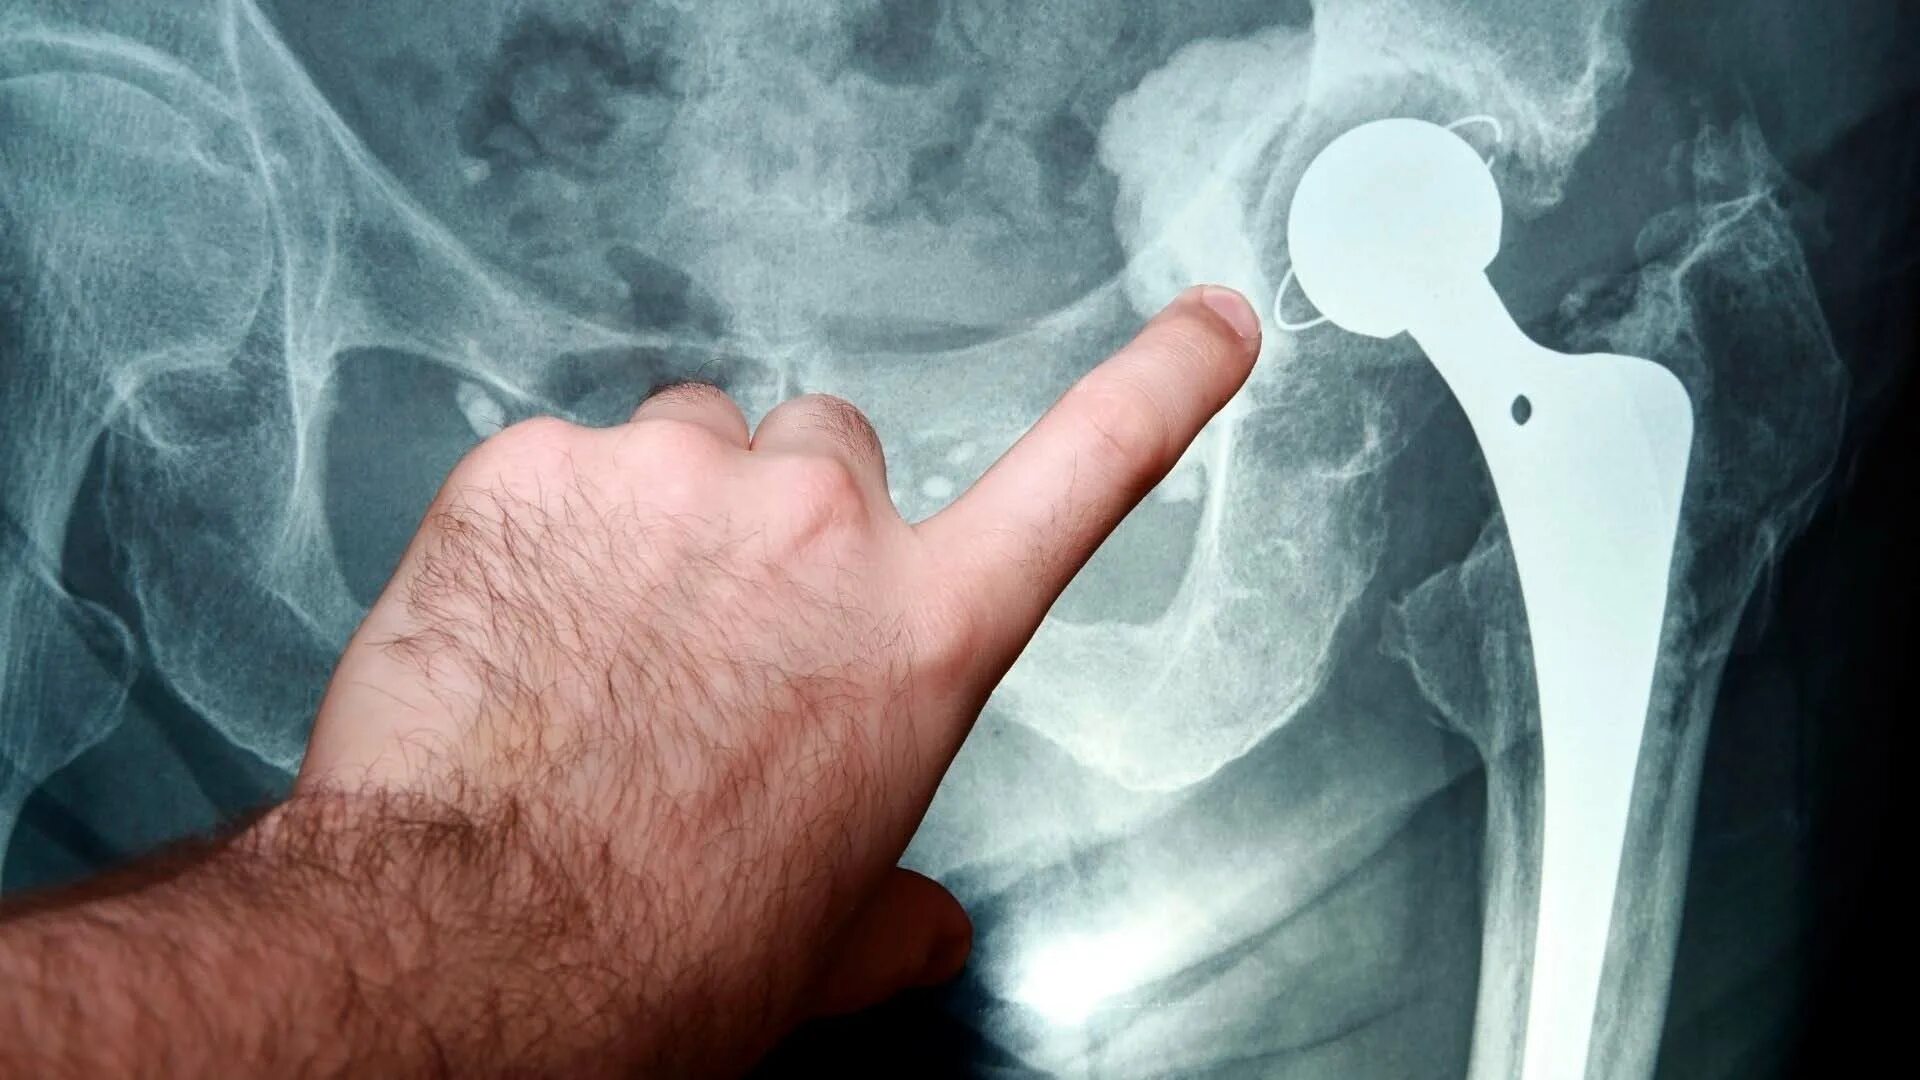

При коксартрозе дают инвалидность